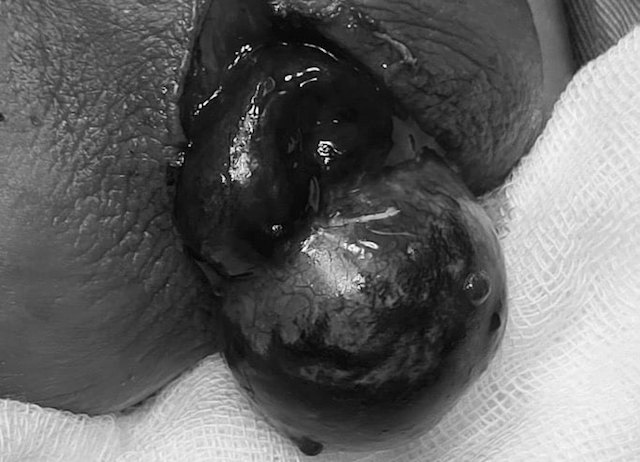

Tinh hoàn tím đen buộc phải cắt bỏ của một bệnh nhân bị xoắn tinh hoàn

Bệnh nhân được chẩn đoán: Xoắn tinh hoàn ngày thứ 3, chỉ định mổ cấp cứu. Tuy nhiên khi phẫu thuật, tinh hoàn phải đã hoại tử tím đen do xoắn trong bao thừng tinh 2 vòng.

Phẫu thuật viên bắt buộc phải cắt tinh hoàn phải của bệnh nhân trong sự tiếc nuối. Giá mà bệnh nhân vào viện sớm hơn, được chẩn đoán sớm hơn thì tình huống có thể đã khác.